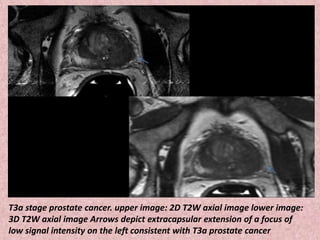

T3a stage prostate cancer. upper image: 2D T2W axial image lower image:

3D T2W axial image Arrows depict extracapsular extension of a focus of

low signal intensity on the left consistent with T3a prostate cancer